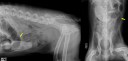

Corps étranger 1 – Réponse

22 avril 2012